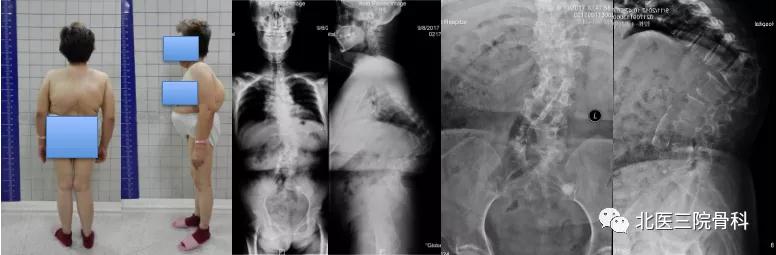

病例三

陈旧结核性胸腰椎后凸畸形

大体照及影像学(术前)

大体照及影像学(术后)

自本世纪初开始,陈仲强教授针对胸腰椎畸形展开积极探索,先后应用经关节突椎间隙联合椎弓根闭合截骨、前方垫高-后方闭合截骨矫形和节段切除-双轴旋转矫形等手术方法,分别针对陈旧创伤性胸腰椎后凸、先天性脊柱后凸和陈旧结核性脊柱后凸等疑难病症进行矫形手术治疗并取得良好疗效,特别是在脊柱陈旧结核性角状后凸领域取得了重大进展,其治疗难度和效果达到国际领先水平,获得北京市科技技术奖和北京市科委首都十大疾病重大科技进展创新奖。